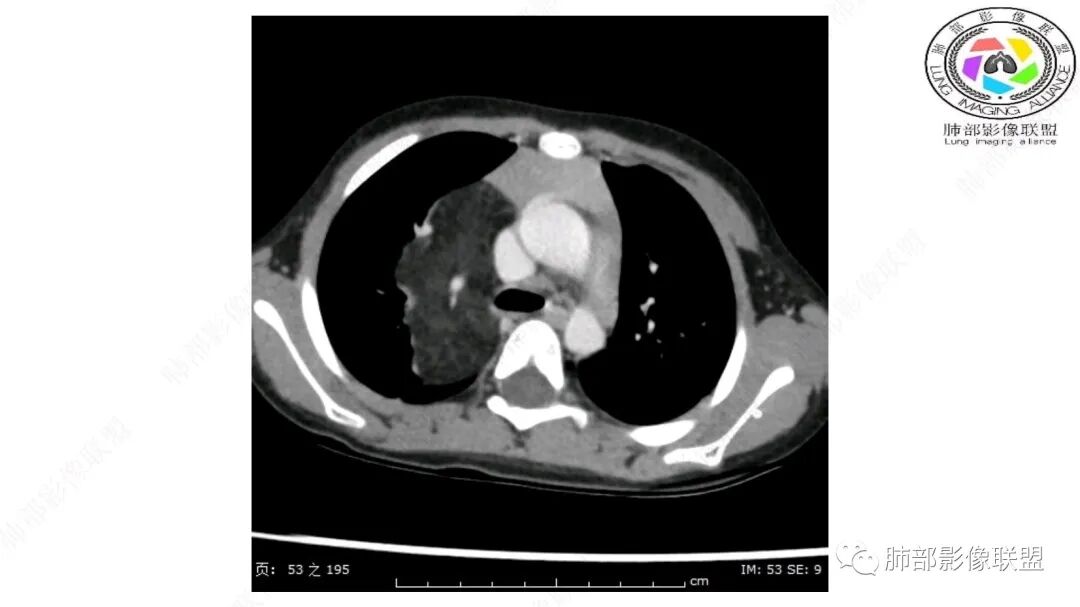

右上纵隔混杂密度肿块,边缘光整,与纵隔分界清,其内多发脂肪密度,增强无明显强化,其内血管穿行,考虑纵隔脂肪母细胞瘤,鉴别畸胎瘤,脂肪肉瘤。

三岁小儿,右侧纵隔巨大脂肪密度肿块,肺动脉穿行其中,密度欠均匀,未见明确实性成分,纵隔脂肪母细胞瘤,冬眠瘤鉴别纵隔脂肪增多症(多弥漫对称)。

患儿3岁 咳嗽检查发现纵隔占位。右肺上叶受压表现,占位以脂肪组织密度为主,似见分隔,首先考虑为脂肪母细胞瘤,鉴别脂肪瘤,畸胎瘤。

幼儿,右上纵膈团块,脂肪密度,内见分隔,增强病灶内见血管穿行,结合患者年龄,考虑脂肪母细胞瘤,鉴别脂肪瘤。

跨肺门,包绕肺血管分支,邻近肺组织受压肺不张。

可以看到造影剂进入的丛状结构

密度不均,非纯脂肪成分。斑片状密度略高区域有轻度填充式强化。

婴幼儿,病变较大,跨肺门,分叶,富含纤维或黏液、含成熟脂肪,破坏力弱或无,浸润性生长模式不明显,未见远处转移。

病灶属于交界区,主体位于肺内,占位效应明显,前方突入胸壁,胸腺受压变形,胸膜显示欠清楚;病灶包绕上叶肺动脉;似乎有体动脉供血。符合肺内的点:包绕上叶肺动脉分支;符合纵隔的点:前方似乎突入胸壁,与胸腺关系比较密切,但是与上腔静脉的关系提示病灶不支持纵隔来源,前纵隔的常规会将上腔静脉受压后移、外移,这是不符合的。

内部血管明显,部分病灶密度增高,单纯脂肪瘤不支持。可惜的是:没有提供CT值:是否强化?如果强化,警惕恶性;胸腺肯定不符合,胸腺会将上腔静脉朝后推移。

2.肺动脉穿行也许是肺内来源最重要支持点!

CT扫描对脂肪类肿瘤常有独到价值。肿块孤立、边界清楚,未见周围浸润,较均匀脂肪样低密度,高度提示为良性!

脂肪母细胞瘤由成熟程度不同的脂肪组织、纤维间隔、黏液基质、小血管丛等间质成分组成,以脂肪组织与黏液样基质为主,其影像学表现取决于上述组织成分。典型的CT和MRI表现为:前后纵隔均可发生,常见于前纵隔;肿块大小不一,直径多在3cm~7cm,密度均匀,CT值呈水样或脂肪密度,脂肪组织密度或信号为主的肿块,其内密度或信号不均匀,可见粗细不一的分隔影,且有结节、片状影,后者可呈轻中度强化;结节状肿瘤包膜完整;弥漫性者包膜不明显,常呈浸润性生长;周围结构为受压和推移改变,可有少量胸腔积液,淋巴结无增大。